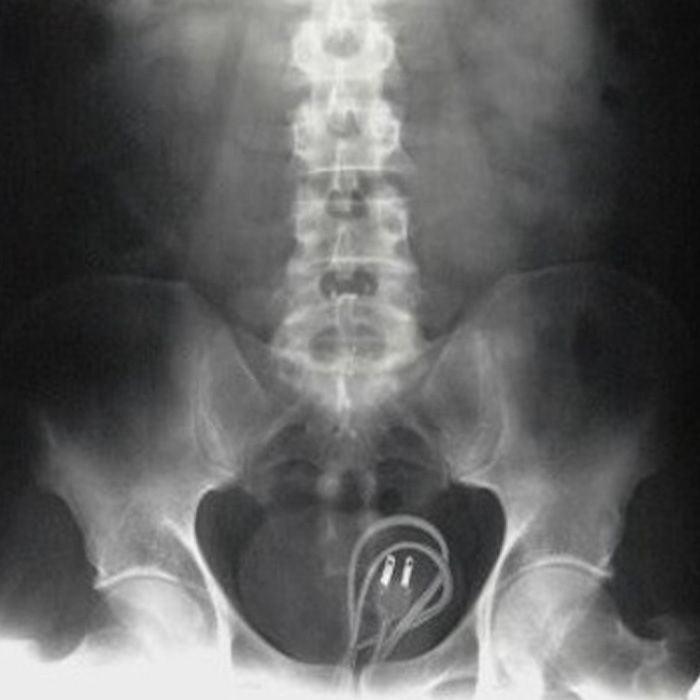

A power cable – because the cell phone was running out of power.